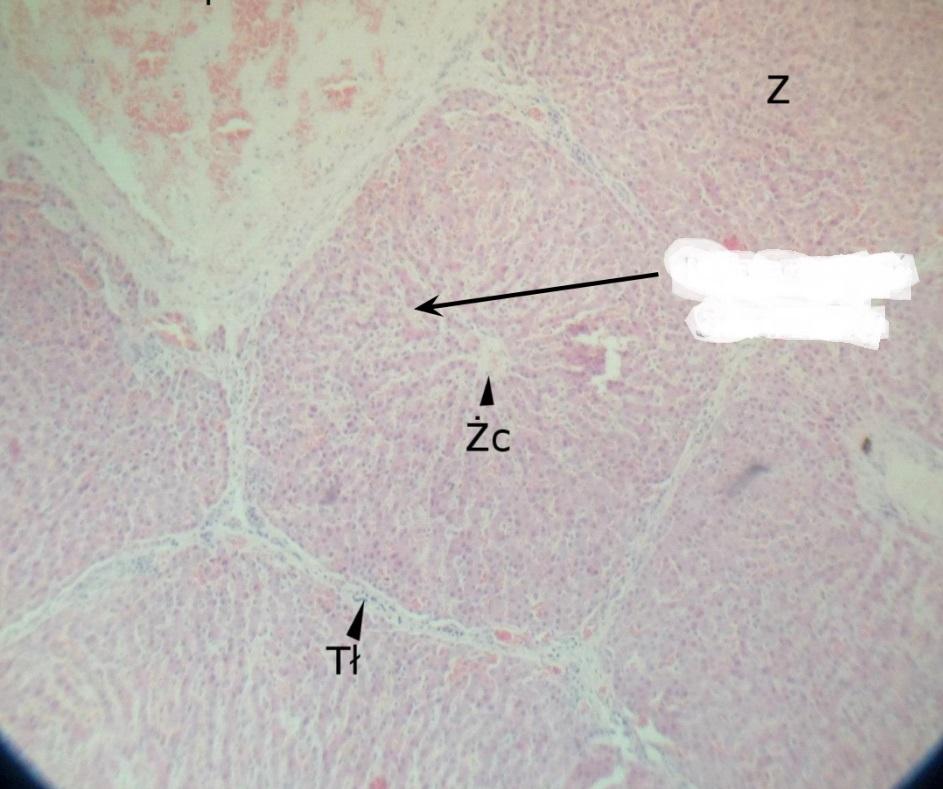

Pytanie 441

żyła centralna (wątroba świni)

Pytanie 442

żyła podzrazikowa (wątroba świni)

Pytanie 443

lokalizacja triad (wątroba świni)